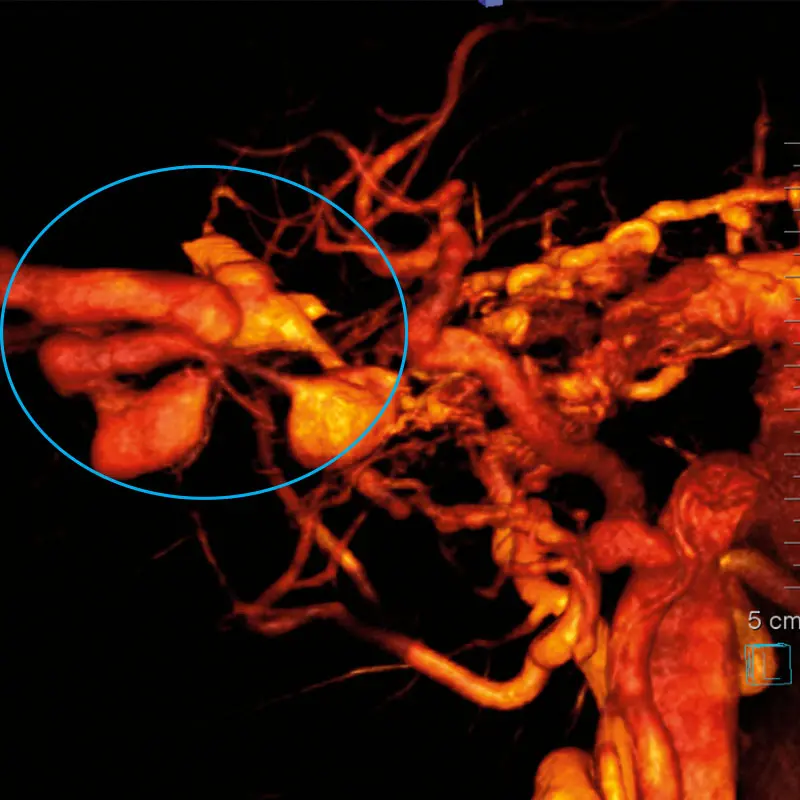

3D reconstruction with angiogram showing the AVM superimposed on skull/orbital bones to identify surgical anatomic relationships

3D reconstruction of an angiogram of the right common carotid artery showing large orbital AVM (circled)